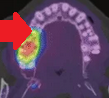

PET Scan. Μεταστατικό καρκίνωμα στη δεξιά υπερώια αμυγδαλή (Ευγενική παραχώρηση Dr. V. Penopoulos).

PET scan ολόκληρου σώματος. Παθολογική πρόσληψη στη δεξιά υπερώια αμυγδαλή (Ευγενική παραχώρηση Dr. V. Penopoulos)